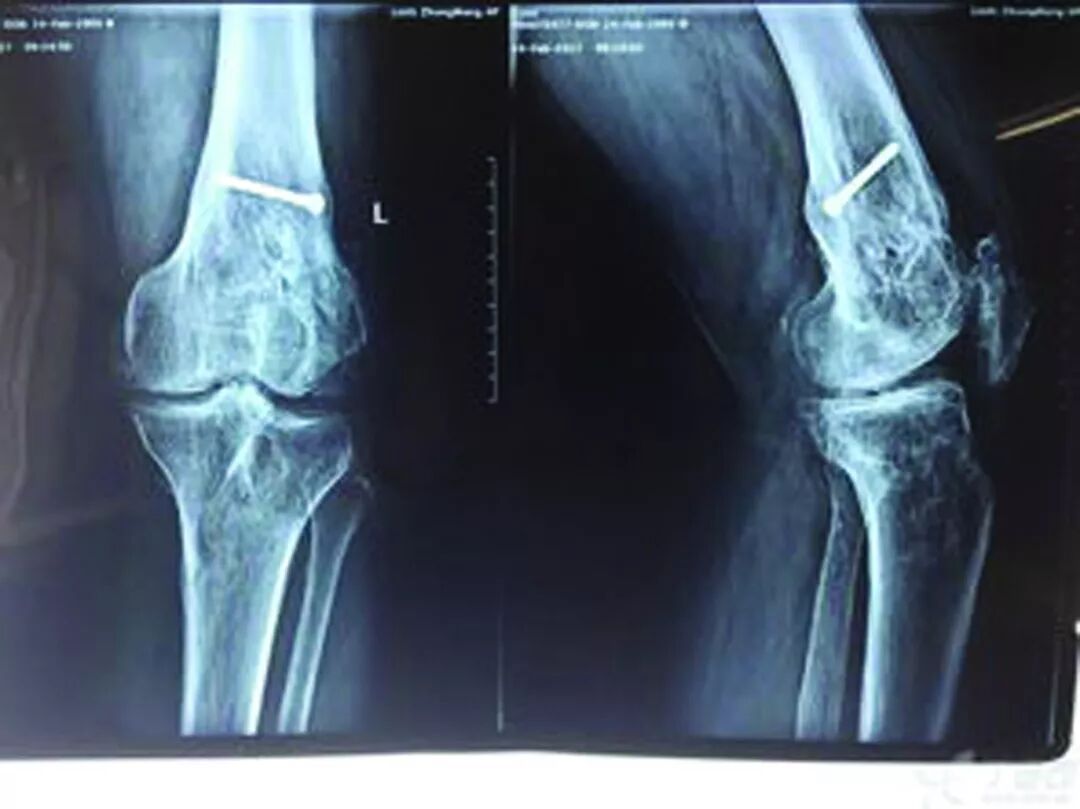

膝关节炎,被称为磨损性和撕裂性关节炎,是一种关节软骨磨损而导致的关节软骨自然缓冲作用消失的情况。骨关节炎是关节炎中最常见的一种。即使是年轻人也可能会出现,但45岁之后患骨关节炎的几率会大大增加。女性比男性更易患骨关节炎。

骨关节病

久坐或久蹲后起立、上下楼时,关节疼痛明显,休息后缓解。

男性患者多,好发于膝关节。发作时肿胀疼痛、皮温高、功能受限。X线片表现半月板、关节软骨面钙化。